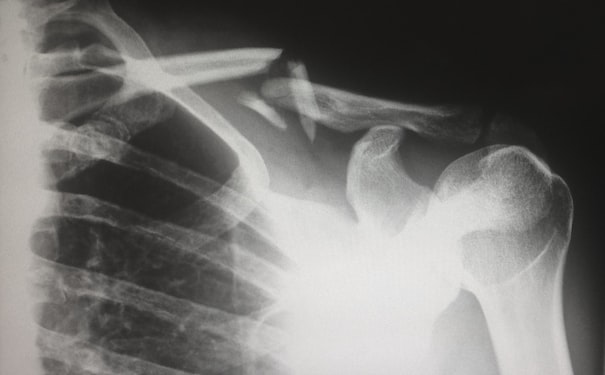

醫(yī)學(xué)模型3D建模軟件可以創(chuàng)建各種類型的醫(yī)療模型,如骨骼、器官和血管等。這些模型有助于醫(yī)生更好地理解人體結(jié)構(gòu)和功能,以便針對(duì)疾病進(jìn)行更準(zhǔn)確的診斷和治療。例如,通過在3D模型上標(biāo)記病變區(qū)域,醫(yī)生可以更容易地規(guī)劃手術(shù)和治療方案。

手術(shù)規(guī)劃

3D打印技術(shù)可以將醫(yī)學(xué)模型轉(zhuǎn)化為物理模型,這對(duì)手術(shù)規(guī)劃和術(shù)前演示非常有用。醫(yī)生可以在3D模型上模擬手術(shù)操作,調(diào)整手術(shù)計(jì)劃并提前預(yù)測(cè)可能的并發(fā)癥。這種方法可以減少手術(shù)風(fēng)險(xiǎn),提高手術(shù)效果。